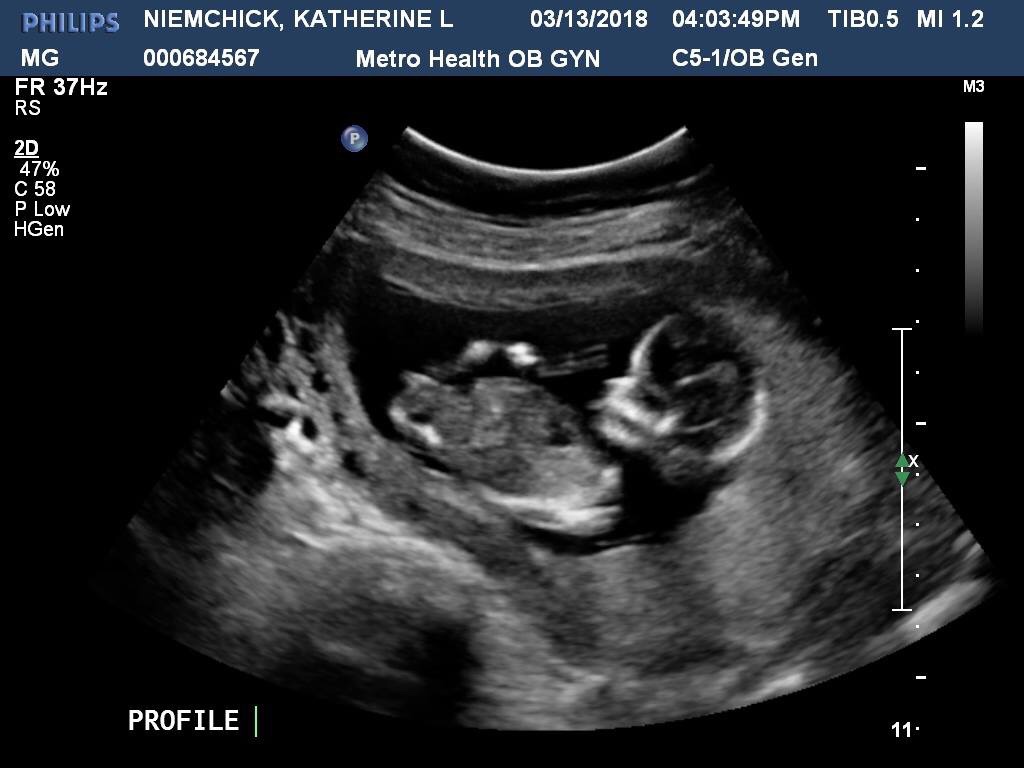

The ultrasound tech said she couldn’t see anything between the legs, but wouldn’t give a prediction. Can anyone tell? Thank you!!Attachment 38988Attachment 38989Attachment 38990

I can see a girl nub

I think girl! :)

Looks girly

girl lean for me to based on 2nd pic

It was confirmed a GIRL at our 20 week scan!!